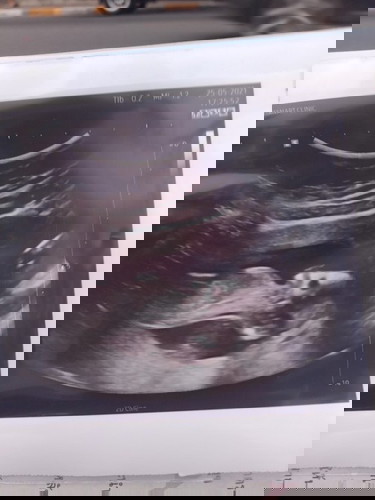

13w+3 เห็นเพศกันรึยังคะ

แม่บ้านไหนเห้นเพศบ้างรึยังค่ะ อยากรู้ค่ะ แม่บ้านนี้หมอบอกน้องน่าจะผู้ชาย #ขอบคุณล่วงหน้านะคะ

อายุครรภ์ช่วงนี้มีโอกาสเห็นค่ะ แต่ไม่ 100% เพศจะชัดเจนจริงๆคือ 18 week ขึ้นไปค่ะ😊